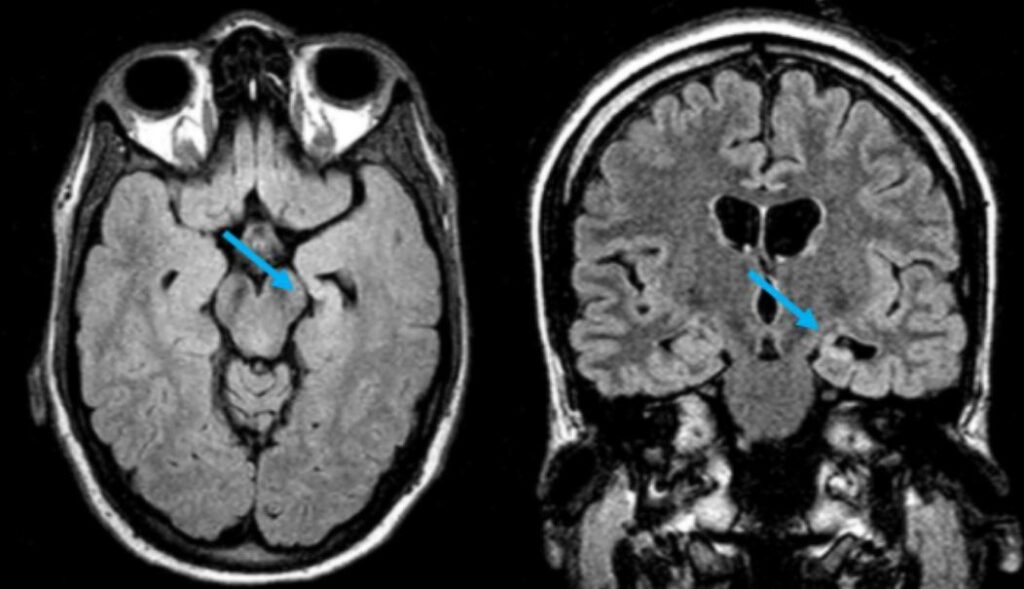

R.M.N. COM ESCLEROSE MESIAL TEMPORAL ESQUERDA: HIPOCAMPO PEQUENO E BRILHANTE, COM PERDA DE ESTRUTURAS INTERNAS (SETA AZUL)